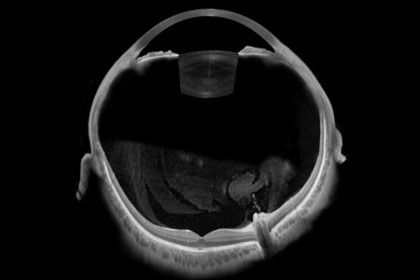

Erfahren Sie mehr wie die präzisen Swept-Source-OCT-Messungen der ANTERION Plattform Sie dabei unterstützen können, Ihre klinischen Arbeitsabläufe zu optimieren und welche Rolle dabei OCT-Bilder spielen.